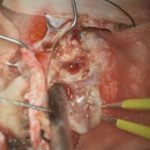

摘出 中